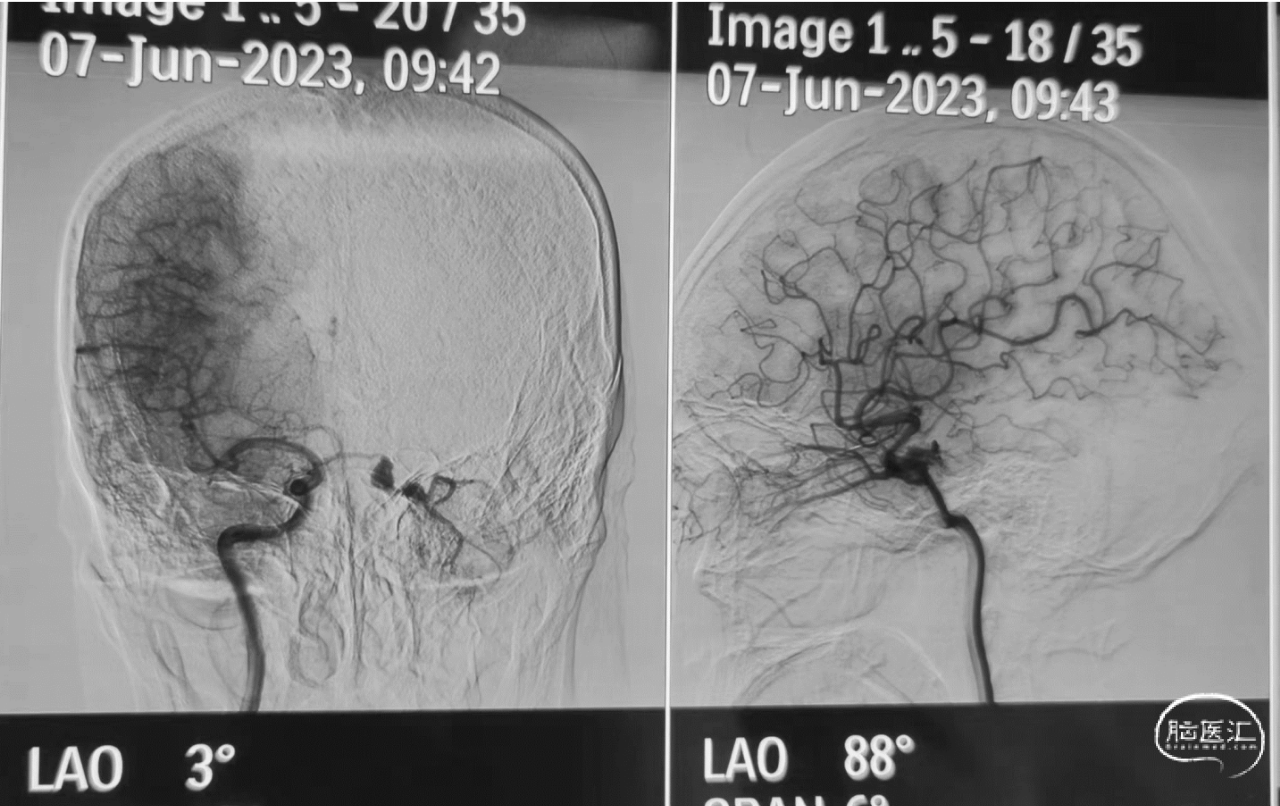

入院时影像检查(外院DSA)及左眼球结膜水肿

诊断:左侧海绵窦区硬脑膜动静脉瘘

手术指征:球结膜水肿严重,影响视力、感染风险高

病例特点:双侧ICA脑膜垂体干供血,眼静脉回流但无汇入近心端静脉主干